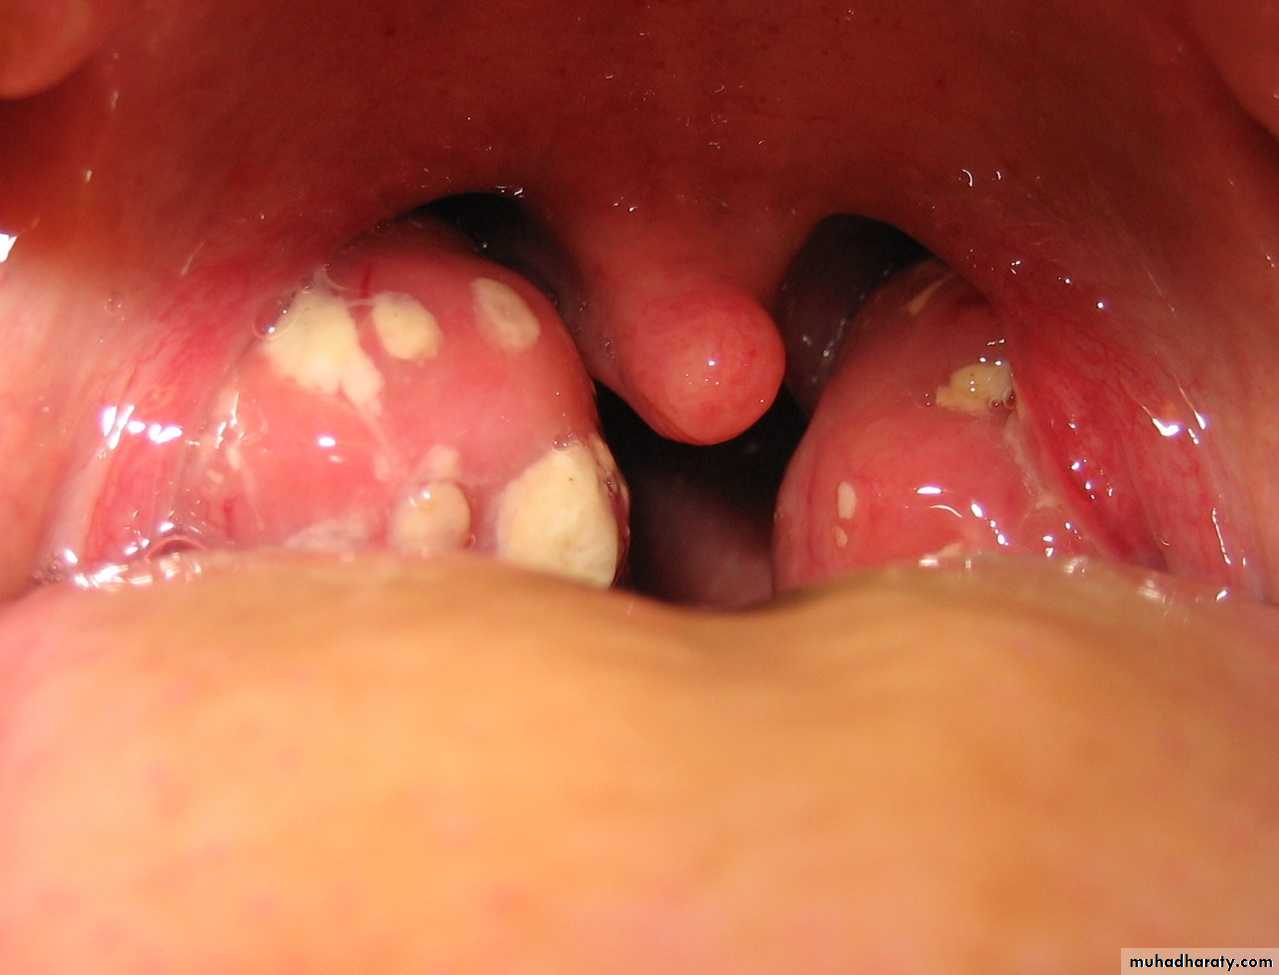

Acute Tonsillitis

Streptococcal pharyngitis

?Quinsy (peritonsillar abscess)